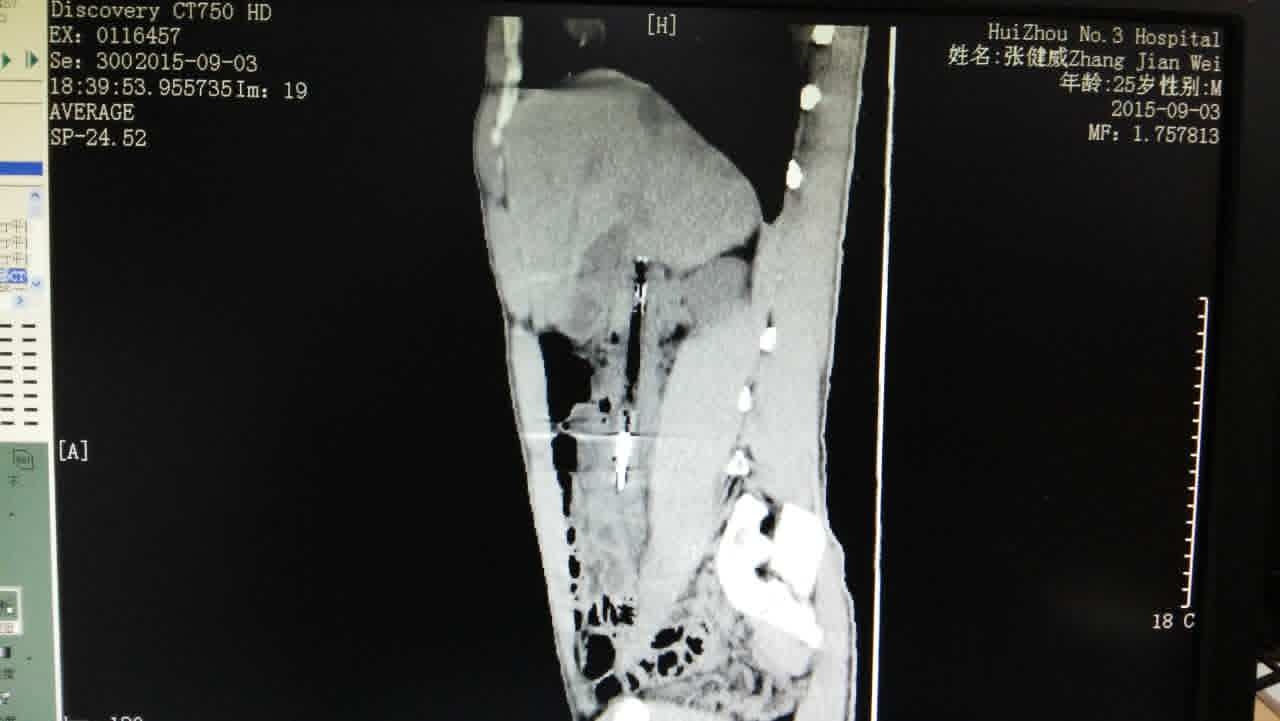

近日,我院在消化內(nèi)科及普通外科的通力合作下,成功為一患者消化道異物取出?;颊?/span>25歲男性,酒后吞食一“圓珠筆”,長(zhǎng)度約15厘米,于第二天在惠州某醫(yī)院行胃鏡下“圓珠筆”取出術(shù),未能成功。吞入圓珠筆第八天到我院就診,經(jīng)過(guò)消化內(nèi)科及普通外科兩個(gè)科室討論,決定在手術(shù)室取異物。因“圓珠筆”已通過(guò)胃進(jìn)入十二指腸并且卡的很牢固,單純內(nèi)鏡下強(qiáng)行拉出易引起十二指腸穿孔,一旦十二指腸穿孔,處理起來(lái)比較棘手。在此情況下,普通外科醫(yī)師通過(guò)腹腔鏡進(jìn)入腹腔,松動(dòng)“圓珠筆”并往胃內(nèi)方向移動(dòng),消化科醫(yī)師通過(guò)胃鏡就比較順利取出這個(gè)定時(shí)炸彈“圓珠筆”。

通過(guò)雙鏡聯(lián)合,避免開腹手術(shù),患者當(dāng)天即恢復(fù)飲食,3天出院,患者所受的創(chuàng)傷最小,恢復(fù)亦最快。當(dāng)然,這離不開醫(yī)院科室之間的合作。好的醫(yī)療團(tuán)隊(duì),能使患者所受創(chuàng)傷最小,獲益最大。(消化內(nèi)科 曹輝瓊)